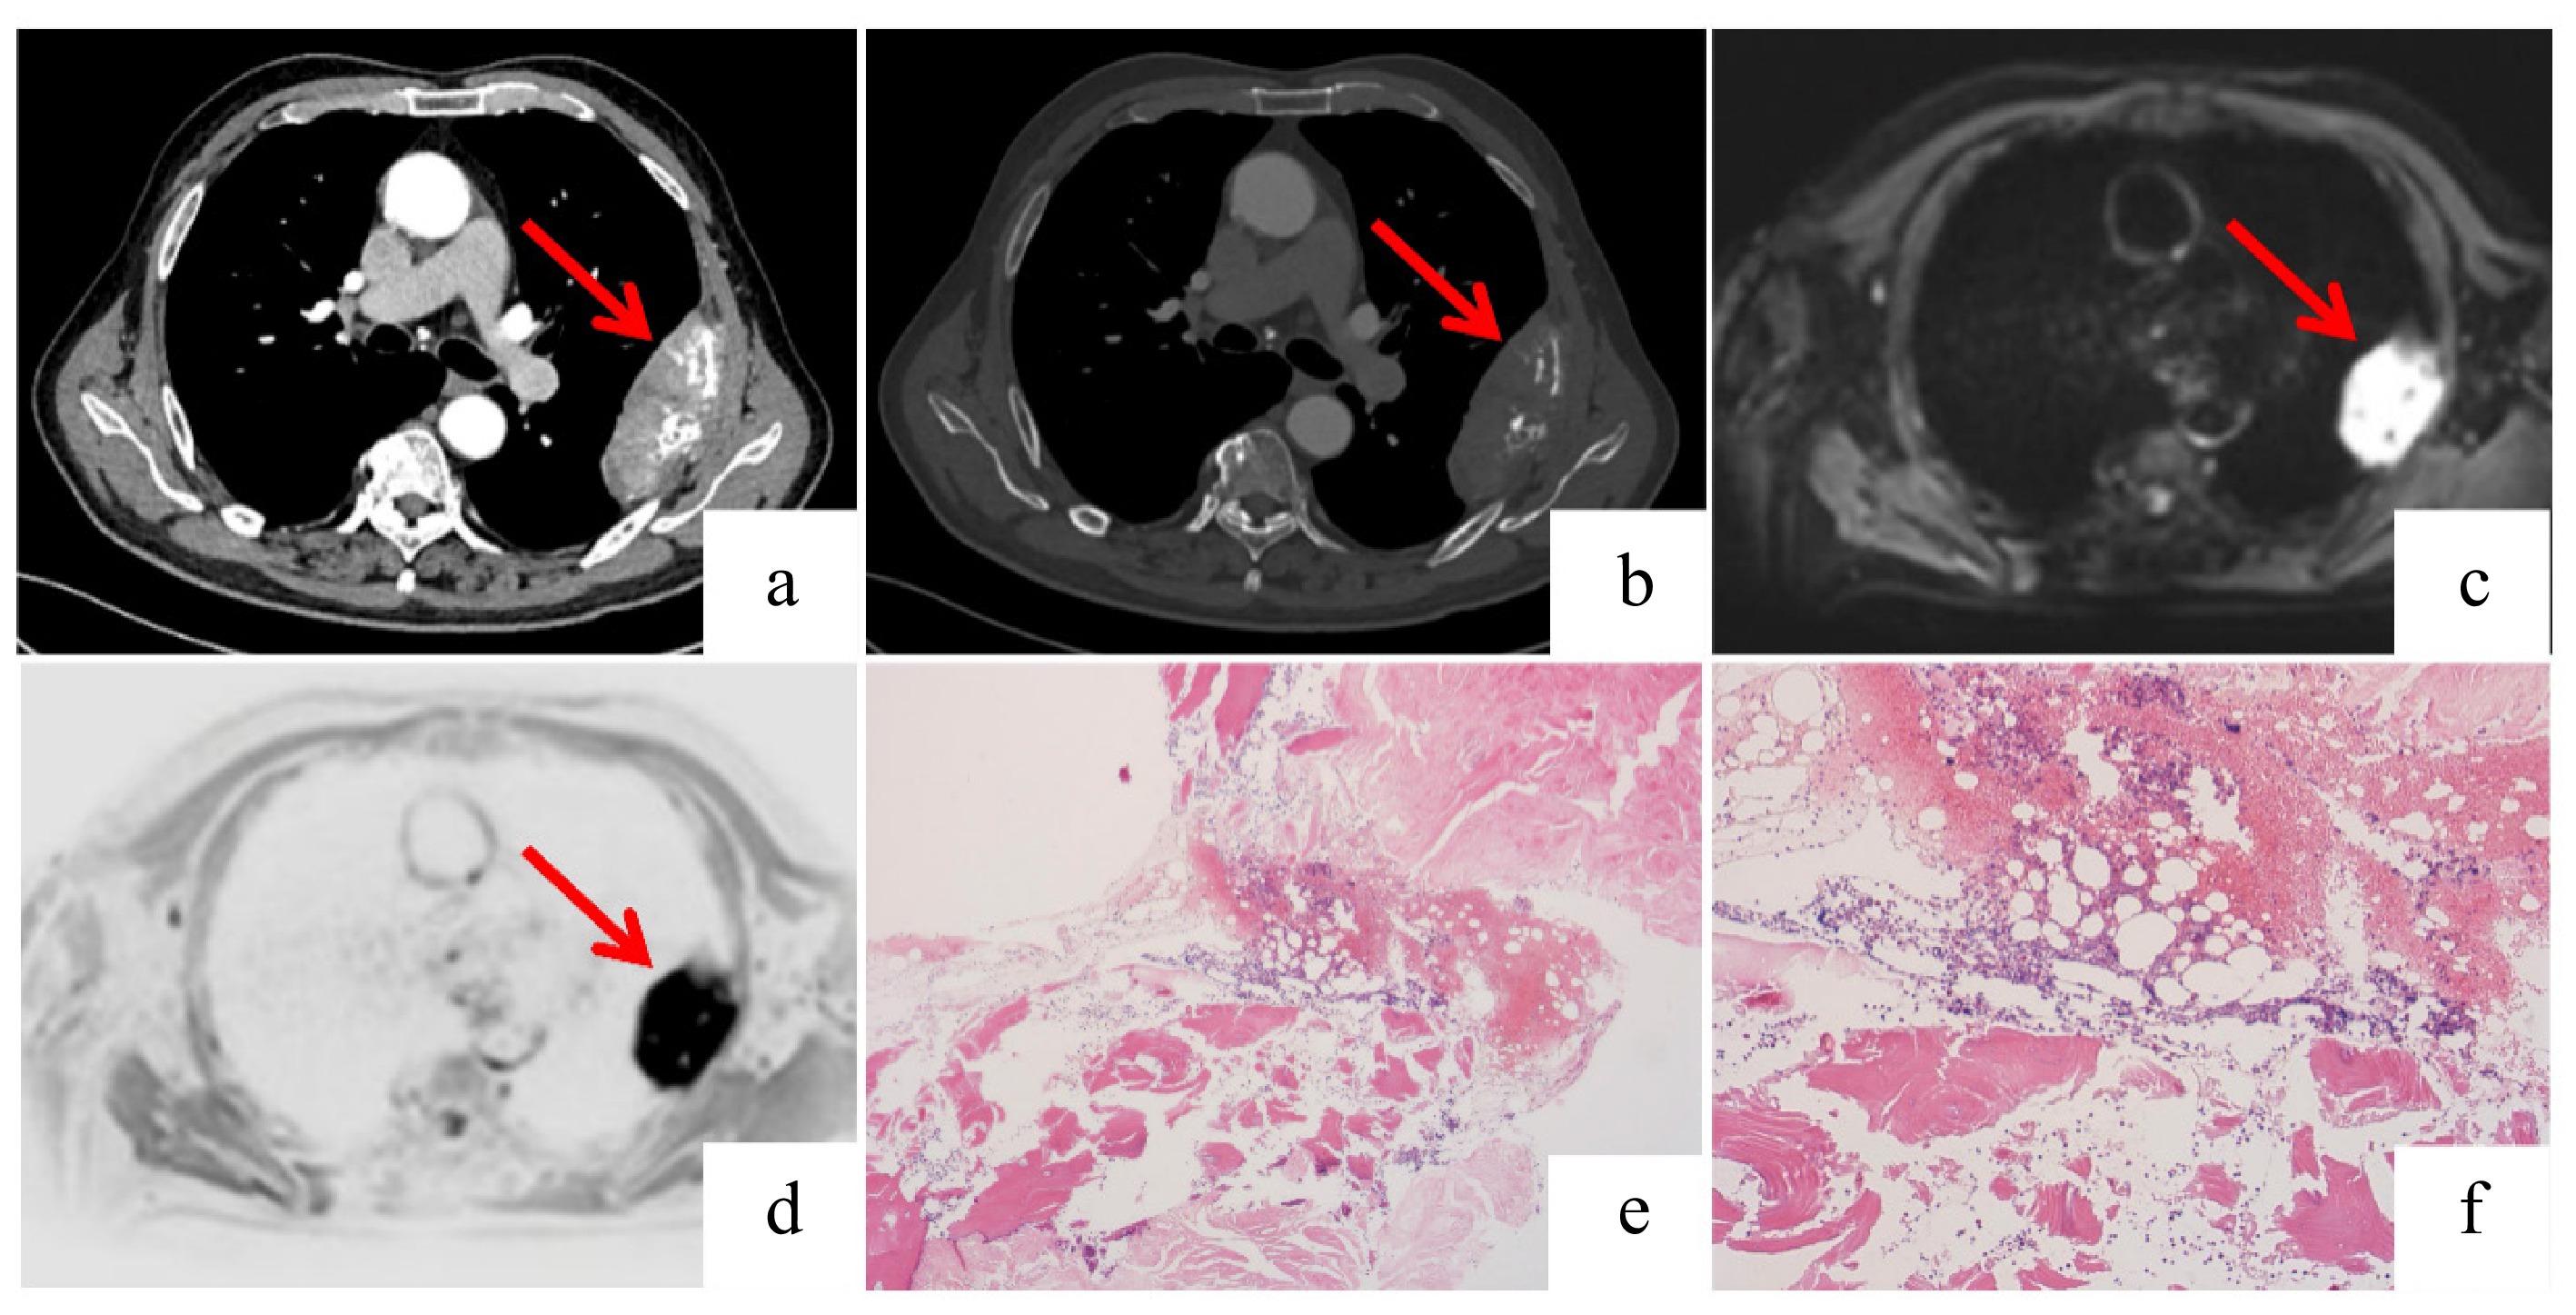

A 74-year-old man was admitted to a local hospital following the acute onset of right-sided limb weakness. Brain magnetic resonance imaging (MRI)–diffusion-weighted imaging (DWI) revealed an AMCI involving bilateral anterior and posterior circulations (Fig. 1). Initial laboratory investigations demonstrated an elevated serum carcinoembryonic antigen (CEA) level of 12.68 ng/mL (normal range: 0−5.2 ng/mL) and a significantly reduced hemoglobin level of 88 g/L (normal range: 130−175 g/L), indicative of anemia and potential malignancy.

Figure 1.

Brain magnetic resonance imaging–diffusion-weighted imaging (MRI-DWI) demonstrated multiple cerebral infarctions involving both the anterior and posterior circulations. Acute infarction in (a) the left anterior cerebral artery (ACA) region, (b) the left middle cerebral artery (MCA) region, (c) the left posterior cerebral artery (PCA) region, and (d) the right MCA region.

To elucidate the underlying etiology, contrast-enhanced computed tomography (CT) of the chest and abdomen was performed. The scans revealed irregular wall thickening in the ileocecal region (Fig. 2b) and a concomitant destructive mass in the left pleural cavity with adjacent rib erosion (Fig. 3a, b), both highly suggestive of malignant processes.

Figure 3.

Imaging and histopathological findings of the plasmacytoma. (a), (b) Axial and coronal contrast-enhanced chest CT scans demonstrating irregular left pleural thickening (measuring approximately 9.8 × 3.1 cm in the maximum cross-section) with associated destruction of the adjacent rib. (c), (d) Fusion positron emission tomography (PET)-MRI images reveal a rounded mass in the left chest wall showing hyperintensity on DWI with corresponding hypointensity on the apparent diffusion coefficient (ADC) map, consistent with restricted diffusion. Increased signal intensity is also noted in the adjacent rib on the MRI sequence. (e), (f) The bone marrow biopsy specimens show scattered plasma cells with lambda light chain restriction indicated by immunohistochemistry: (f) lambda-positive; (e) kappa-negative. This confirmed the presence of monoclonal plasma cells. The overall cellularity and number of plasma cells were not significantly increased.

The patient was subsequently transferred to our institution for comprehensive management. Colonoscopy identified an ulcerative mass in the ileocecal area (Fig. 2a), and a histopathological examination via an endoscopic biopsy confirmed a moderately differentiated ileocecal adenocarcinoma (Fig. 2c, d). Concurrently, a biopsy of the left rib mass was conducted. The histological analysis revealed sheets of monomorphic plasma cells (Fig. 4a, b). Immunohistochemistry (IHC) showed that the neoplastic cells were strongly positive for CD38 and CD138 (Fig. 4c, d) and exhibited lambda light chain restriction (kappa-negative, lambda-positive) (Fig. 4e, f). Although his bone marrow morphology showed only 1% plasma cells, and flow cytometry did not detect a monoclonal population, the presence of clonal lambda-restricted cells supported a diagnosis of plasmacytoma. Whole-body MRI was performed to differentiate between solitary bone plasmacytoma (SBP) and multiple myeloma (MM), revealing no other bony lesions or distant metastases (Fig. 3c, d). A bone marrow biopsy further confirmed minimal involvement (Fig. 3e, f).